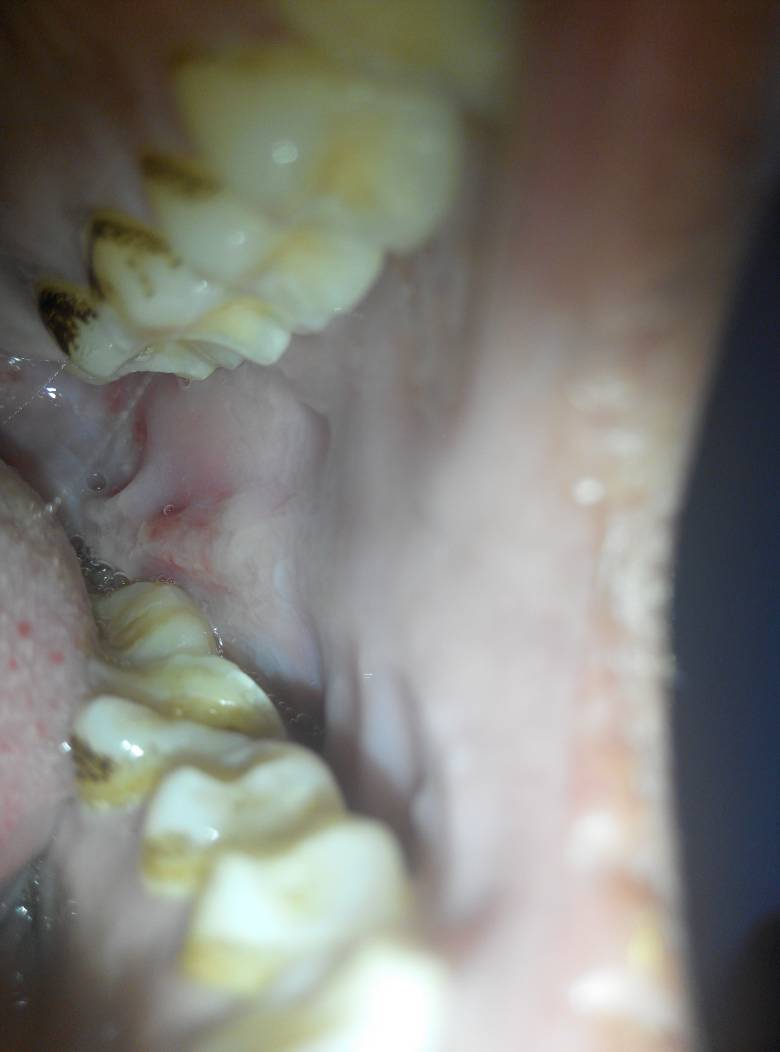

问:口腔内侧肿了一条线,是怎么回事啊

内壁肿痛,今天肿痛更严重,而且起床貌似还出现一点脓,请问是怎么了?